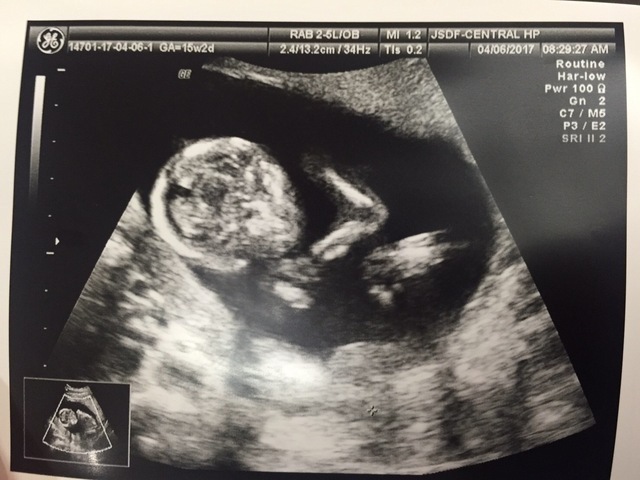

15週1日(15w1d・男の子)|ちゃまゆり さん(21歳)

エコー写真撮影時のエピソード:

2人目の妊娠でした。

1人目の時に切迫早産で入院経験があり

今回も背中やお腹の痛みがありまた切迫早産になるのかな

と言う気持ちです

急遽病院に行き検査してもらい

予防にと張り止めの薬も出してもらう事になりました。

今わ予防で毎日薬を飲む生活